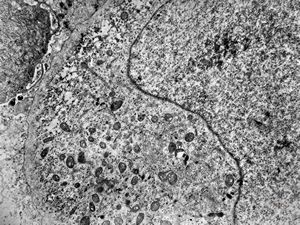

F,50y. | progressive multifocal leukoencephalopathy- viral particles in a glial cell

F,50y. | progressive multifocal leukoencephalopathy- viral particles in a glial cell

F,50y. | progressive multifocal leukoencephalopathy- viral particles in a glial cell